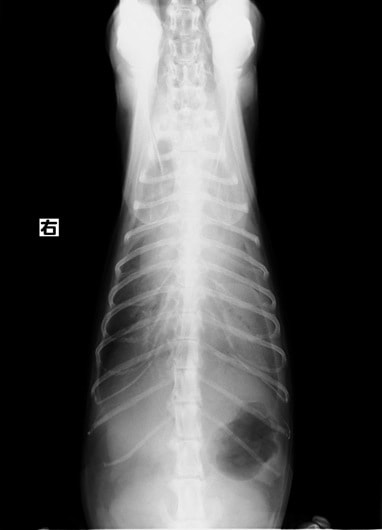

症例:【マルチーズMix 1歳齢 メス】

A:胸部レントゲン写真 正面像

B:胸部レントゲン写真 側面像

左側胸壁よりLevine 4/6の連続性心雑音が聴取された。胸部レントゲン検査において心拡大が認められ、超音波検査においても肺動脈領域に連続的な異常血流が観察された。大学病院を紹介受診され、手術が行われた。現在はACE阻害薬のみの内服で補助的治療を行っている。